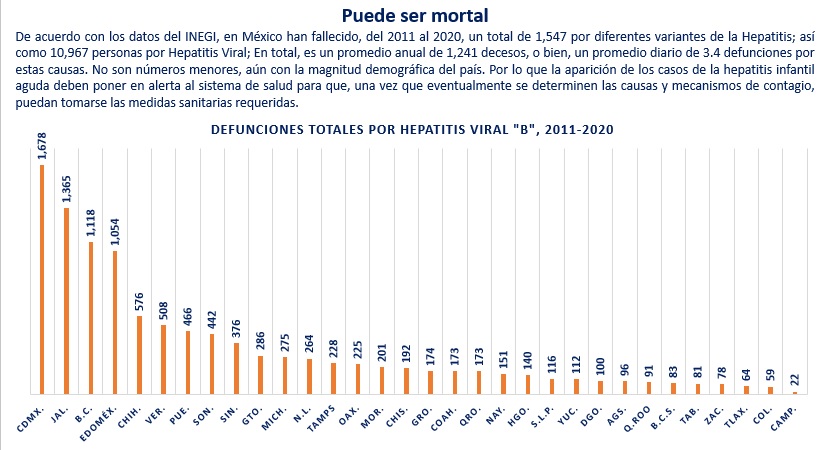

En el caso de la Hepatitis Vírica “B”, la cual, de acuerdo con la Hoja Informativa de la OMS en la materia: “Es una infección vírica que afecta al hígado y puede dar lugar tanto a un cuadro agudo como a una enfermedad crónica… se transmite comúnmente de madre a hijo durante el parto, así como a través del contacto con sangre u otros líquidos corporales…”

De este tipo de enfermedad, se tuvo hasta la semana epidemiológica 52 del 2020, un total de 372 casos. Para la misma fecha de corte, pero del 2021, la cifra fue de 483 casos, de los cuales, 321 se registraron entre hombres y 162 entre mujeres. Comparando las cifras totales de ambos años, el incremento registrado es de 29.8%

Para la semana 18 del 2022 se habían contabilizado 121 casos de hombres y 46 de mujeres, es decir, un total de 167, es decir una cifra 46.4% superior a la del mismo periodo el año previo.